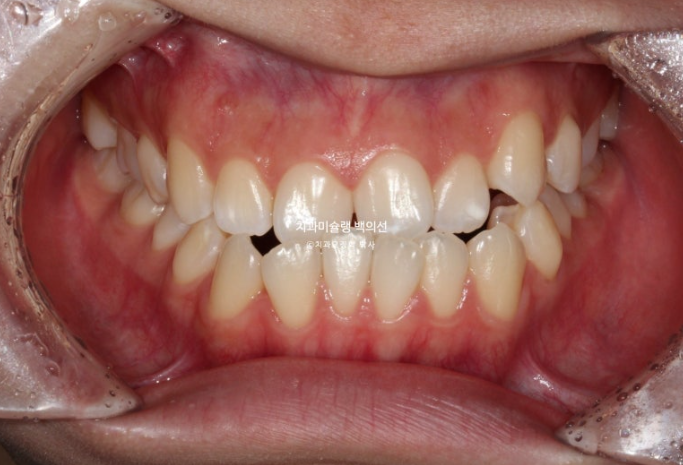

25.10

중심선은 정확히 맞습니다.

물샐틈 없는 1급 교합입니다.